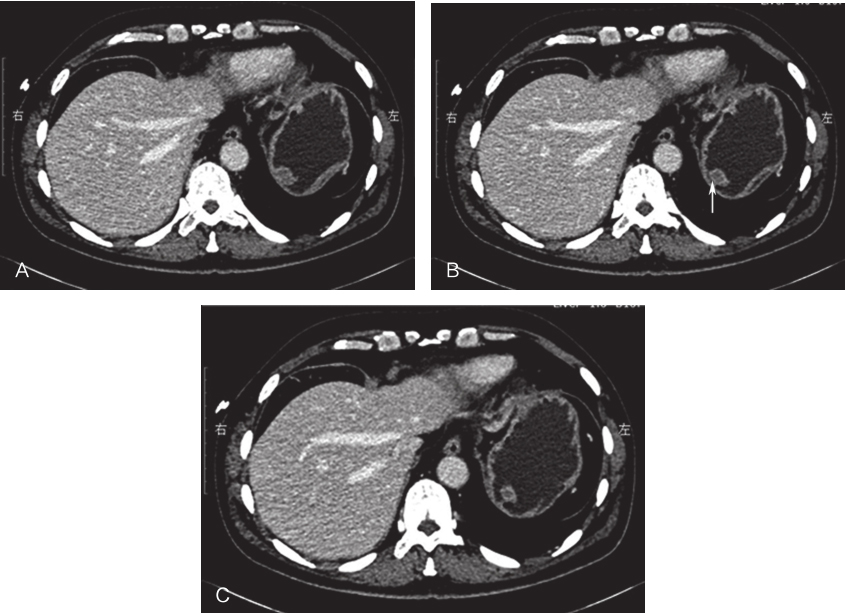

于2017年5月19日行“3D腹腔镜下胃底肿物及部分胃壁楔形切除术”,术中所见:探查腹盆腔未见明显转移结节,肿物位于胃底前壁大弯侧,大小约1.5cm×1cm,游离胃底,于胃底后壁大弯侧见另一肿物,大小约0.5cm(图3),腹腔镜下充分探查其他部位胃壁,未见其他肿物,分别以切割吻合器完整切除两个肿物(图4),术中胃镜下仔细探查胃腔,未见肿物。

图3术中肿物位置

图4切除肿物大体观

A.胃后壁肿物;B.胃前壁肿物